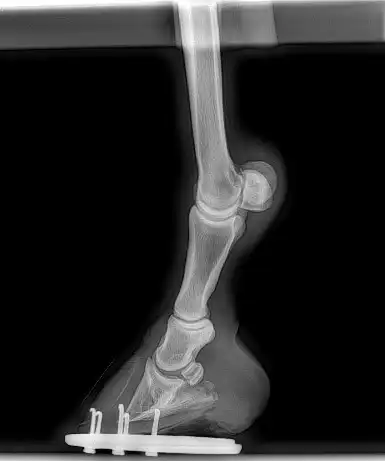

Radiographs should be considered to evaluate the degree of rotation of the pedal bone and the severity of the case. This information can then be used to assess the degree of corrective hoof trimming that is required to rebalance the hoof in collaboration with a farrier.